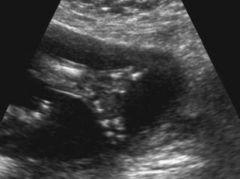

What is the sonographic appearance of duodenal atresia?

Double bubble

polyhydramnios

Duodenal atresia

Double bubble

When can duodenal atresia be seen?

24 weeks

What causes a double bubble?

duodenal atresia

duodenal stenosis

annular pancreas

jejunal atresia